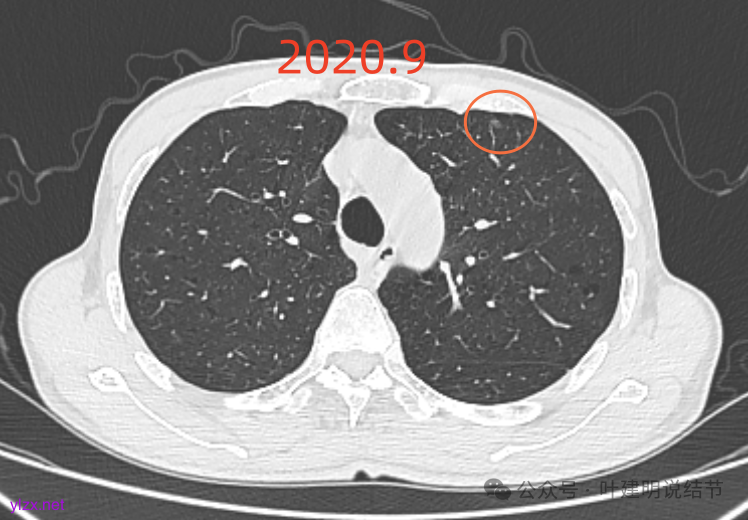

先看2020年9月的片子:

左上胸膜下有处偏长条小结节,也是磨玻璃密度的,轮廓较清。

左上叶前胸壁胸膜下有小结节,磨玻璃密度,有微小血管进入,轮廓与边界清。